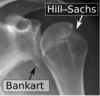

33

25 M W L shoulder injury during contact sport. Dx? Management?

Anterior shoulder dislocation with likely hill sachs deformity humeral head is dislocated anteriorly and inferiorly with some flattening of the corresponding part of the humerus. Tx: Reduce + immobilize with sling x3 withs with early ROM and outpatient ortho follow up

60 F presents with severe right shoulder pain and immobility. She fell down the steps outside her house and landed on her right side two hours prior to presentation. On exam, her right arm is abducted and externally rotated. She has decreased sensation to touch over the lateral aspect of her right shoulder Dx?

anterior shoulder dislocation with bankhart lesion with axillary nerve injury Bony Bankart - avulsion of the anteroinferior glenohumeral ligament with capsulolabral detachment

List 3 fractures to look for in a post-reduction x-ray of a patient with an anterior glenohumeral shoulder dislocation

1. Avulsion of greater tuberosity 2. Hill sachs lesion 3. Bony bankhart